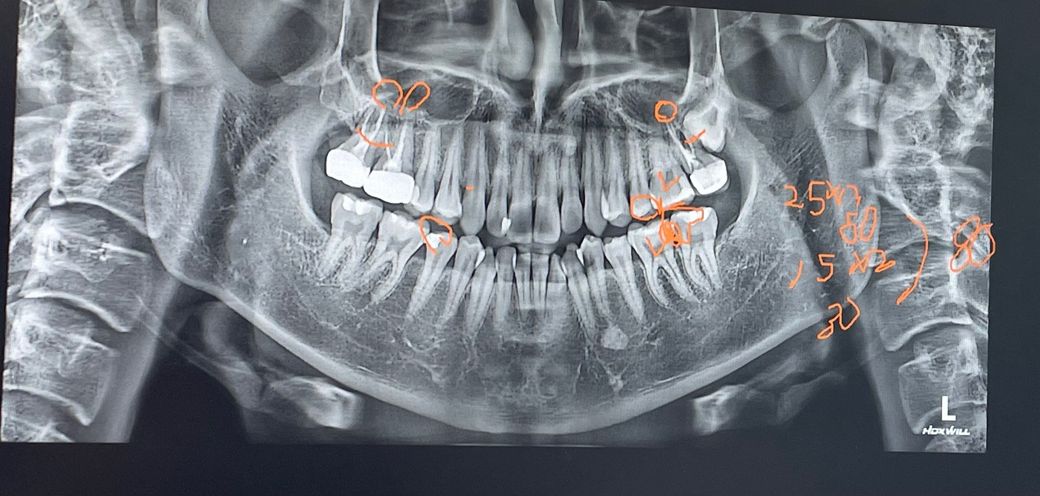

이가 아파서 치과 갔더니 치아 사이에 충치있어서 하나는 인레이 25만원 그 옆 치아는 레진으로 15만원 해서 40만원인데 레진이 이렇게 비싼가요;;;

• 1번 째 사진

치아 사이 레진은 비용이 많이 나옵니다. 그래서 보통은 인레이로 치료를 많이 합니다. 인레이는 보철치료로 인접면 레진비용보다 더 나오긴합니다.

레진은 비보험 진료라 치과마다 비용은 다를 수 있고요, 면수에 따라 비용이 올라갑니다 보통 2면 레진이면 10~15만원입니다